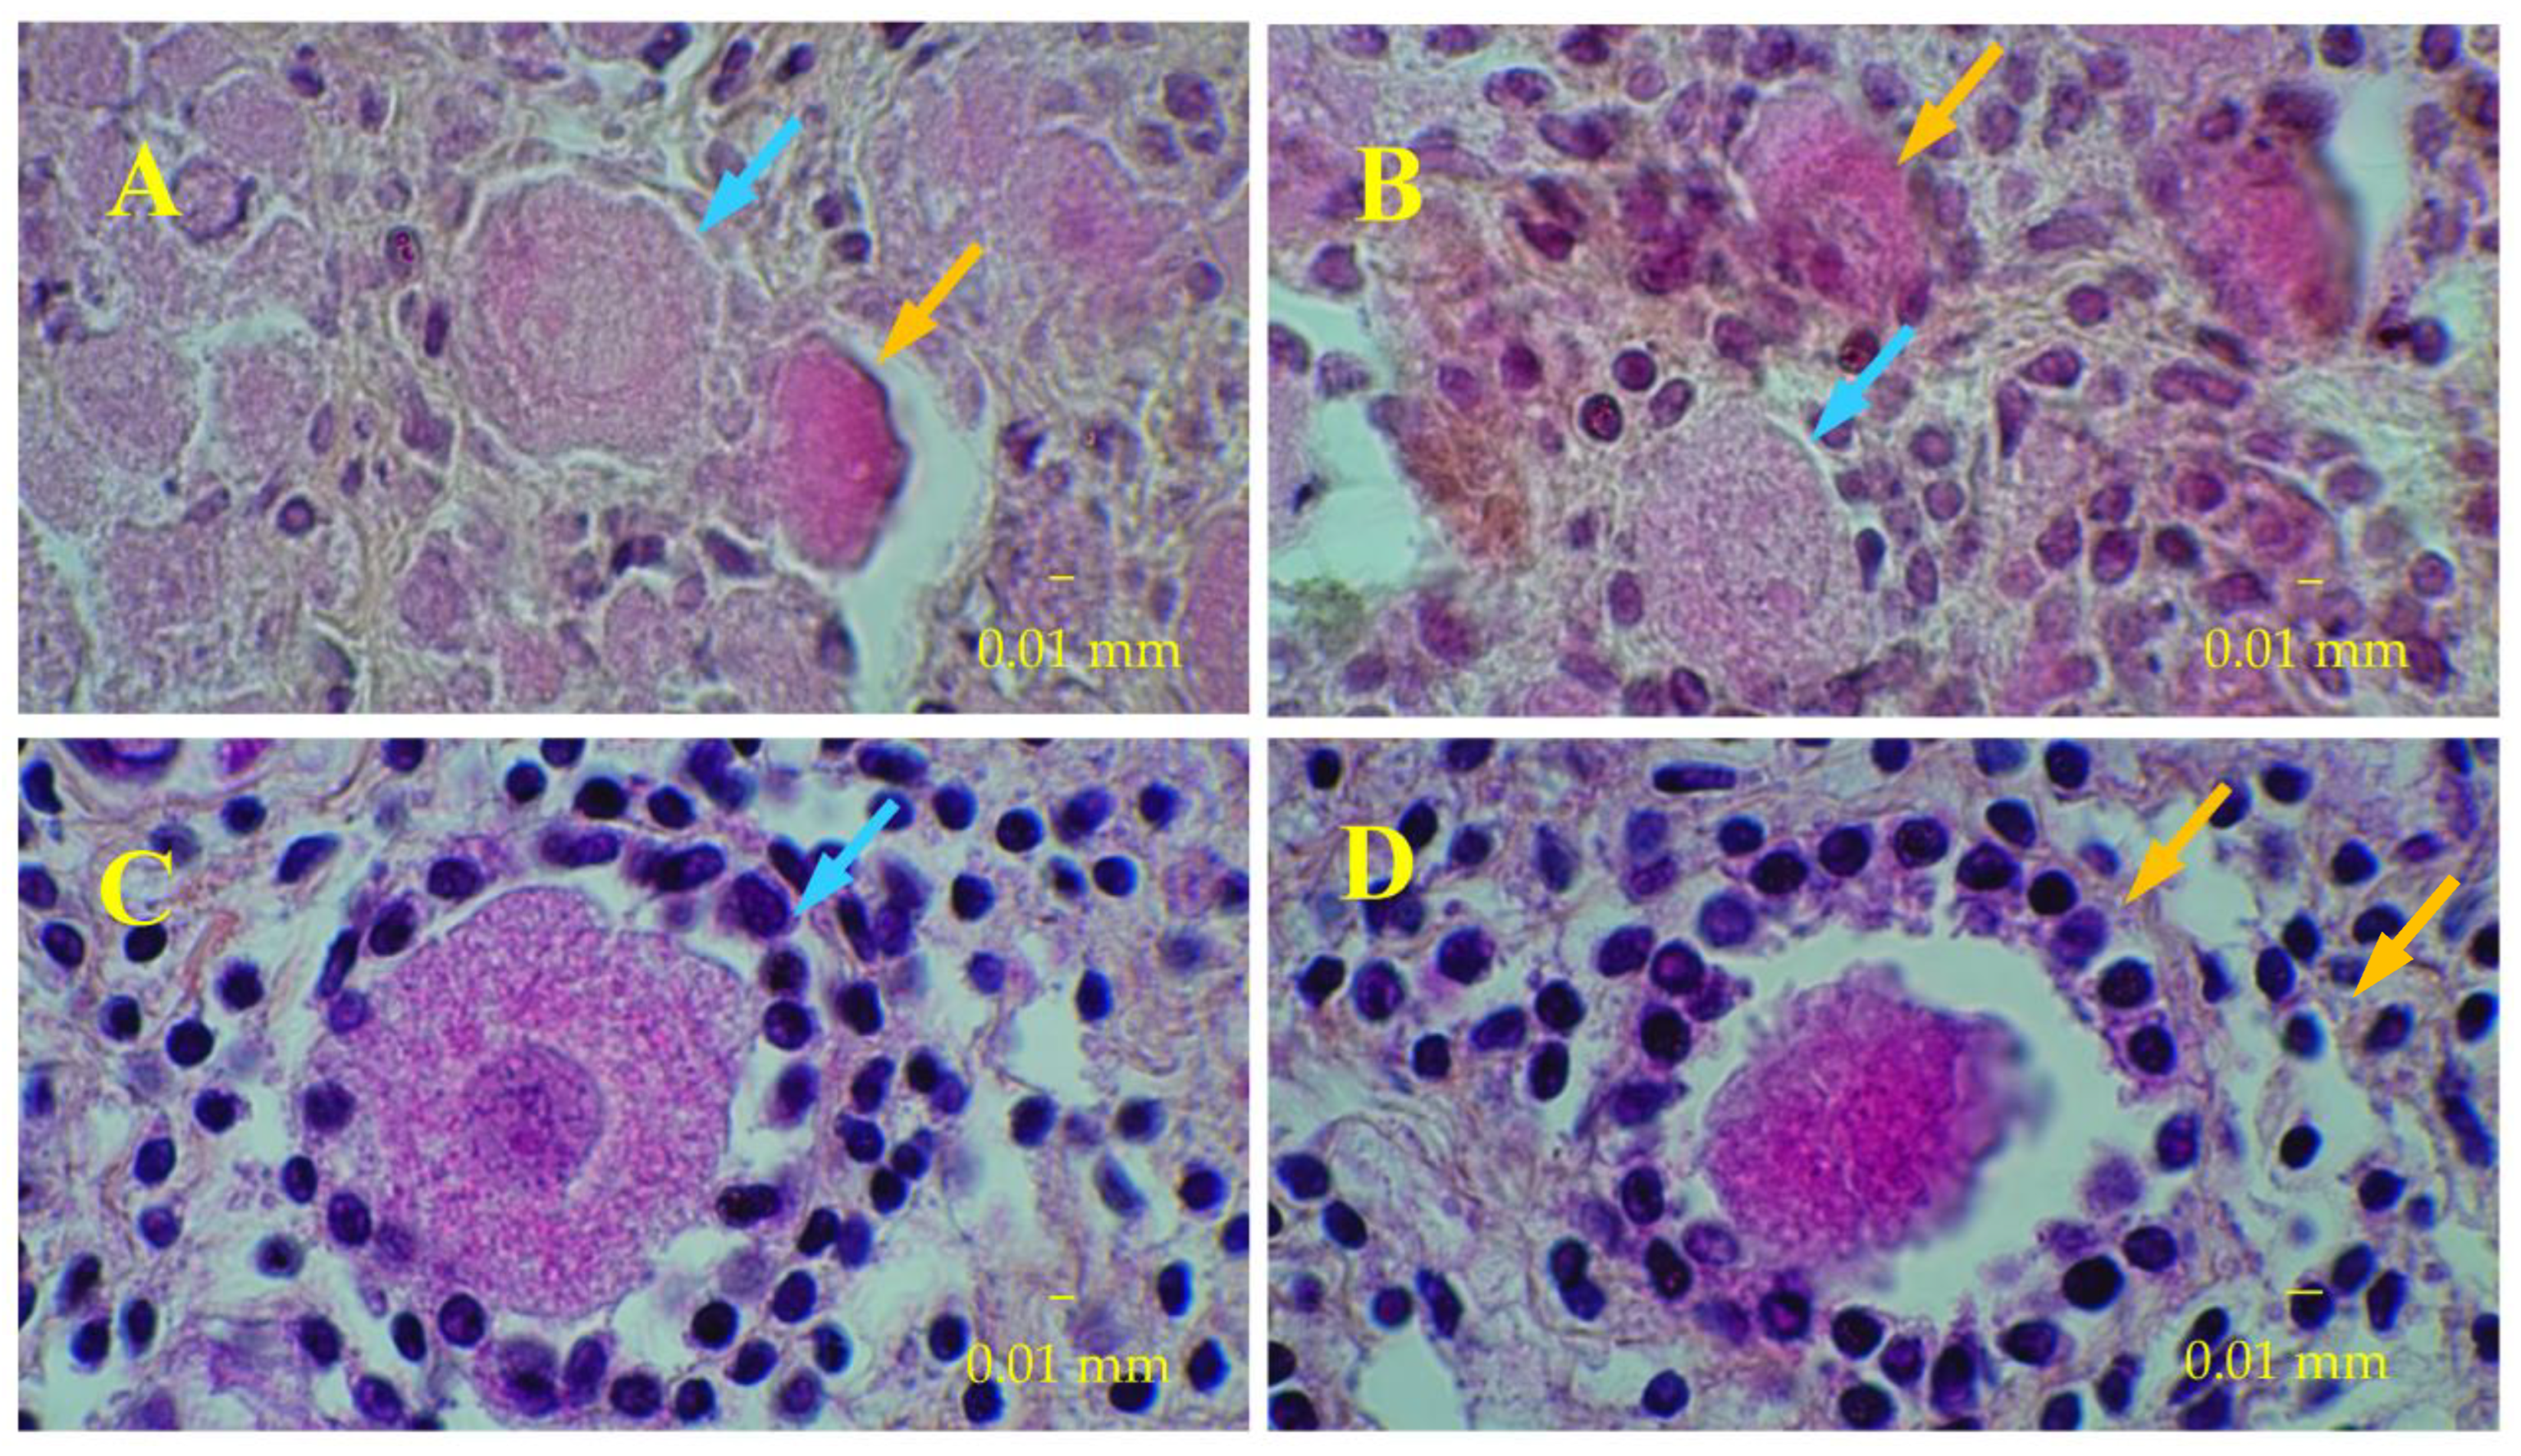

2.4. Histological Analyses

2.5. Immunostaining of Ovarian Tissue Slices

3.3. Immunostaining for Cell Apoptosis